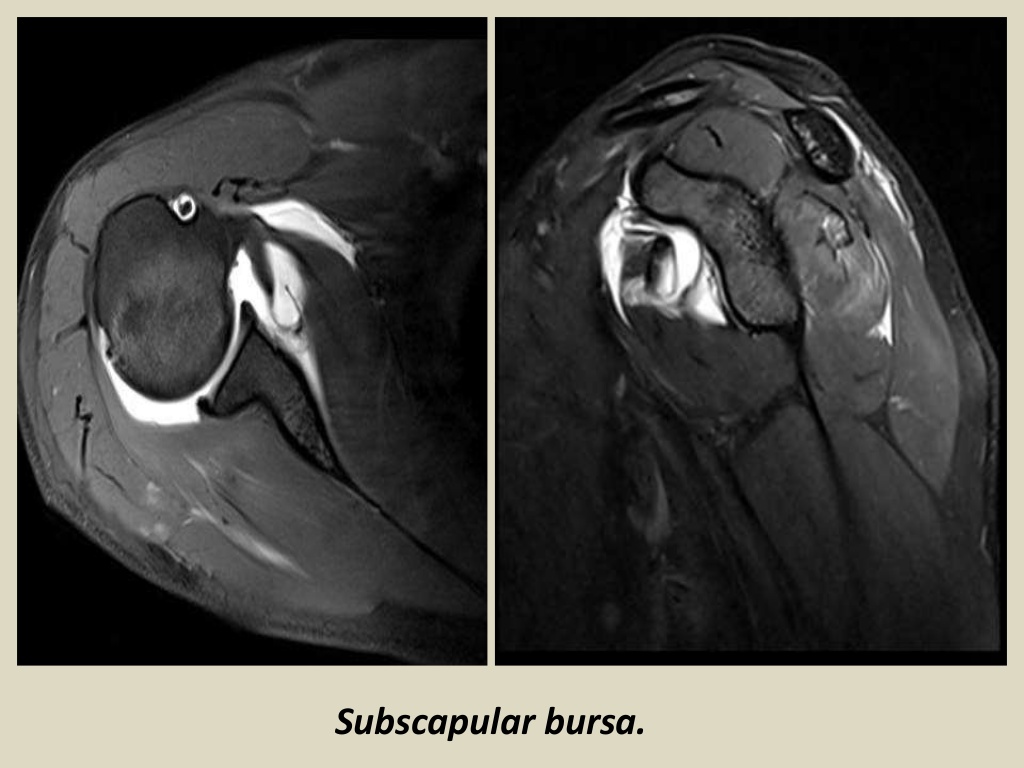

Subscapularis Bursa Mri Shoulder Joint Bursa Radiology diagram of normal bursae surrounding the shoulder joint: As with bursae in general, they. mr imaging is frequently used to examine shoulder disorders. shoulder bursae refer to sacs surrounding the shoulder joint that are filled with synovial fluid. The radiological report should include a description of the following: the subscapularis recess, also known as the superior. Shoulder Joint Bursa Radiology.